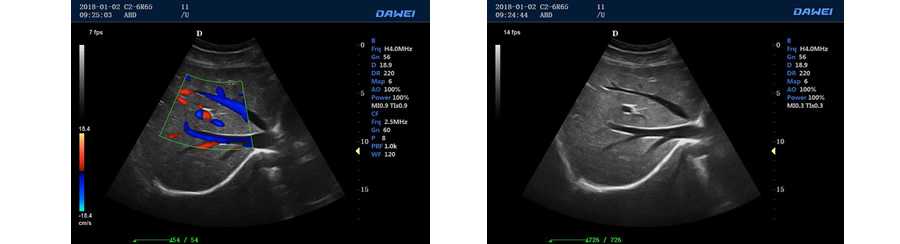

PIP智能畫中畫成像模式

●彩色多普勒血流成像單元

●方向性彩色能量多普勒成像單元